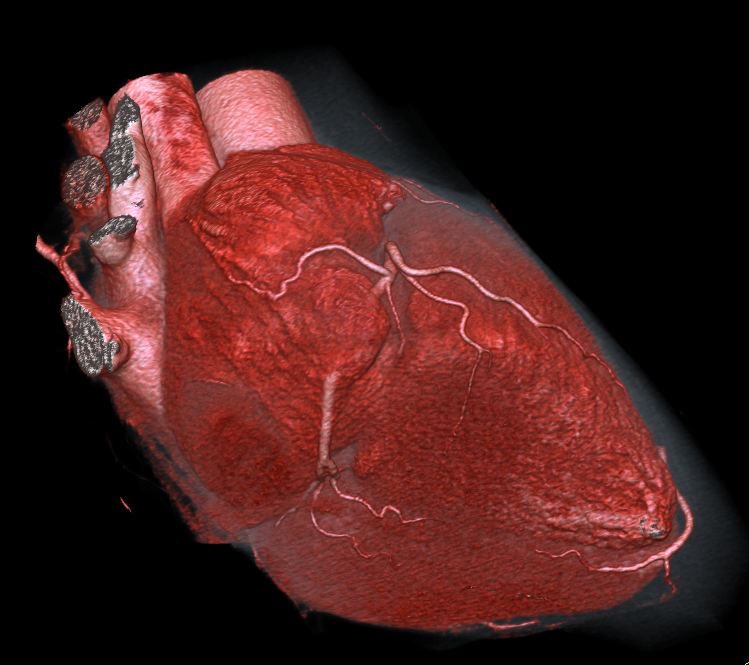

Hypertrophic cardiomyopathy (HOCM) on cardiac CT #cardiotwitter @escardio @M_Ijgua @M_Marwan_ @CardiacCTGuy @Heart_SCCT @FiRSTSCCT @Drroxmehran @mirvatalasnag @HolgerNef @BudoffMd @mgwfriedrich @BayerMatthias @JEscaned @thiele_holger @YoungDgk